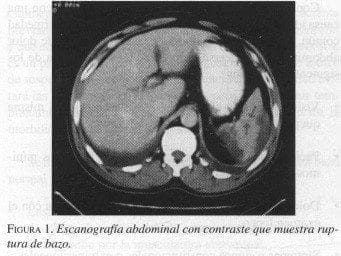

Hombre de 39 años sin antecedentes de importancia, quien ingresó con historia de 10 días de dolor epigástrico irradiado al dorso, acompañado de dolor en hipocondrio izquierdo irradiado al hombro, de inicio súbito, que aumentó progresivamente hasta incapacitarlo. Ecografía de hígado y vesícula biliar normal, excepto por pequeña colección subfrénica izquierda. TAC contrastado de abdomen mostró condensaciones basales pulmonares, pequeña laceración esplénica y hematoma periesplénico (figura 1). Por aumento del dolor abdominal el paciente es llevado a cirugía ese mismo día, encontrándose hemoperitoneo (800 ml) y estallido esplénico con isquemia del mismo, sin otras lesiones en la cavidad abdominal (figura 2). Se realizó drenaje del hemoperitoneo y esplenectomía.